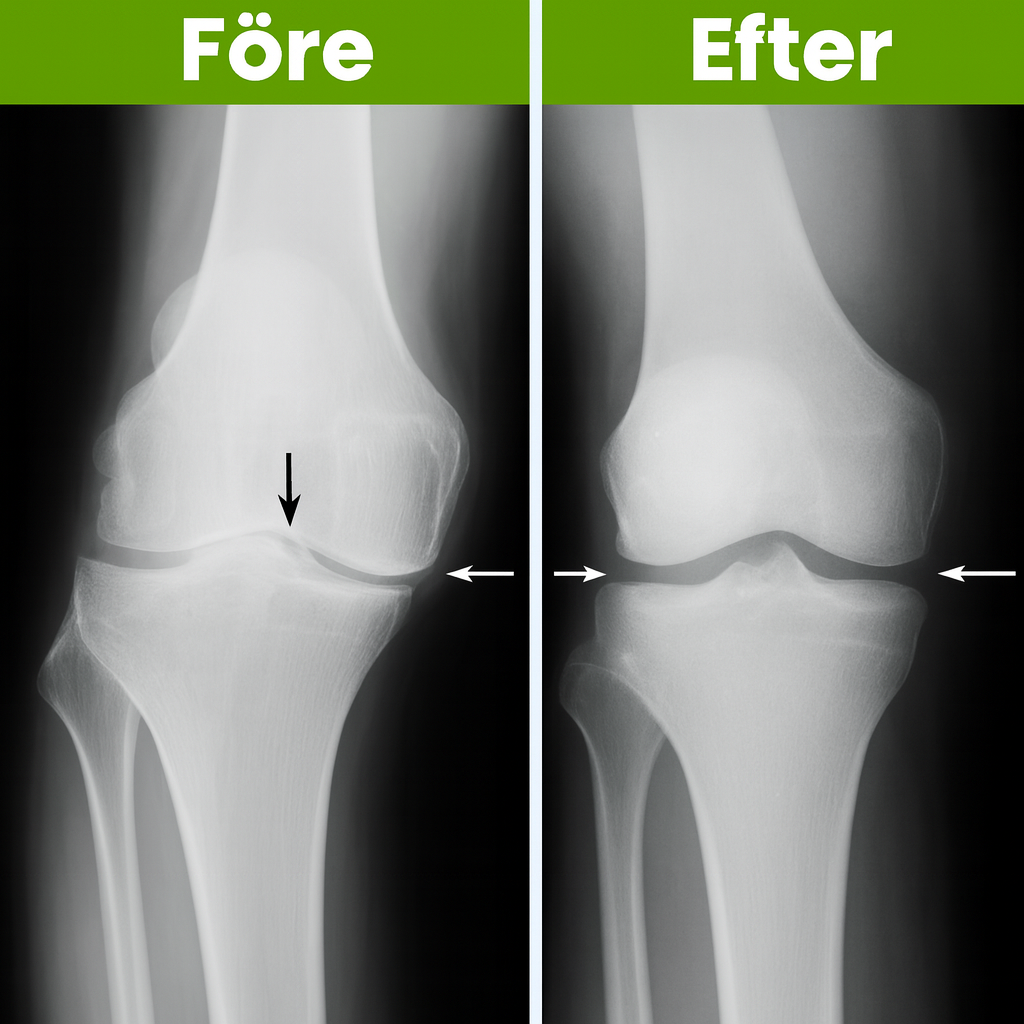

KnäKomfort™ är utformad enligt beprövade ortopediska principer som används i modern rehabilitering. Stödet fokuserar på korrekt knäjustering, stabilisering och riktad kompression – samma metod som ortopeder ofta rekommenderar innan man överväger injektioner eller kirurgiska ingrepp.